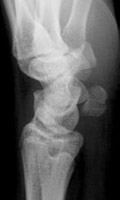

Skeletal Trauma > Hand & Wrist > Quiz

Can you name the fractures below? Click on the button for answers. | |||||